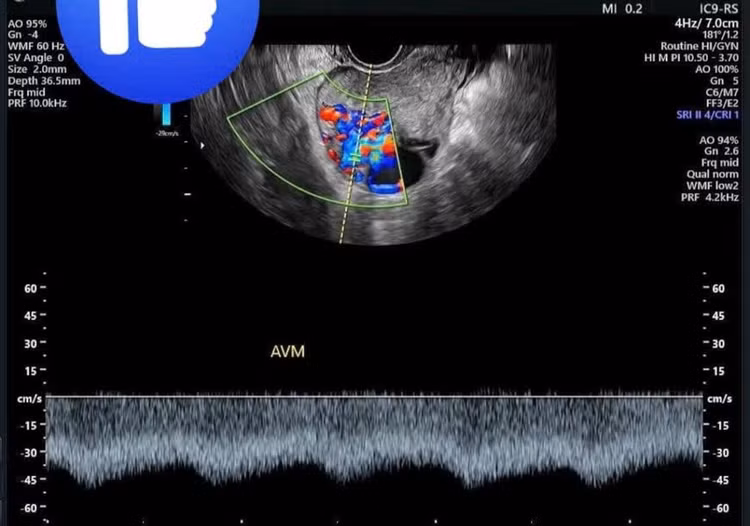

Qua siêu âm nghi ngờ tình trạng thông động tĩnh mạch tử cung, người bệnh tiếp tục được chụp cắt lớp vi tính tiêm thuốc cản quang phát hiện ổ thông động tĩnh mạch trong cơ tử cung kích thước 31x46mm, được cấp máu từ cả động mạch tử cung hai bên và động mạch buồng trứng; tĩnh mạch dẫn lưu về chậu và buồng trứng hai bên.

tu-cung-thong-3.jpg

Hình ảnh thông động tĩnh mạch tử cung (AVM) qua siêu âm - Ảnh BVCC